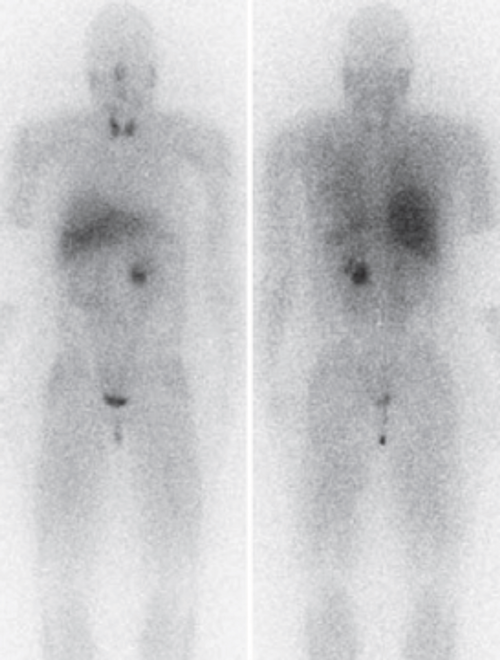

- In view of these risks you perform the shown scan. What is this scan and what does it show?

-

Nuclear medicine metaiodobenzylguanidine (MIBG) scan. Demonstrates a left phaeochromocytoma with no further adrenal or extra-adrenal lesions.